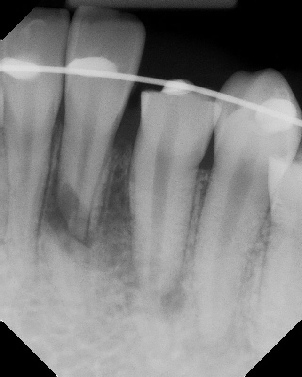

Apicoectomy - Surgical Root Canal Pre-op (post trauma) Coronal segments obturated Apical segments surgically removed 3 years